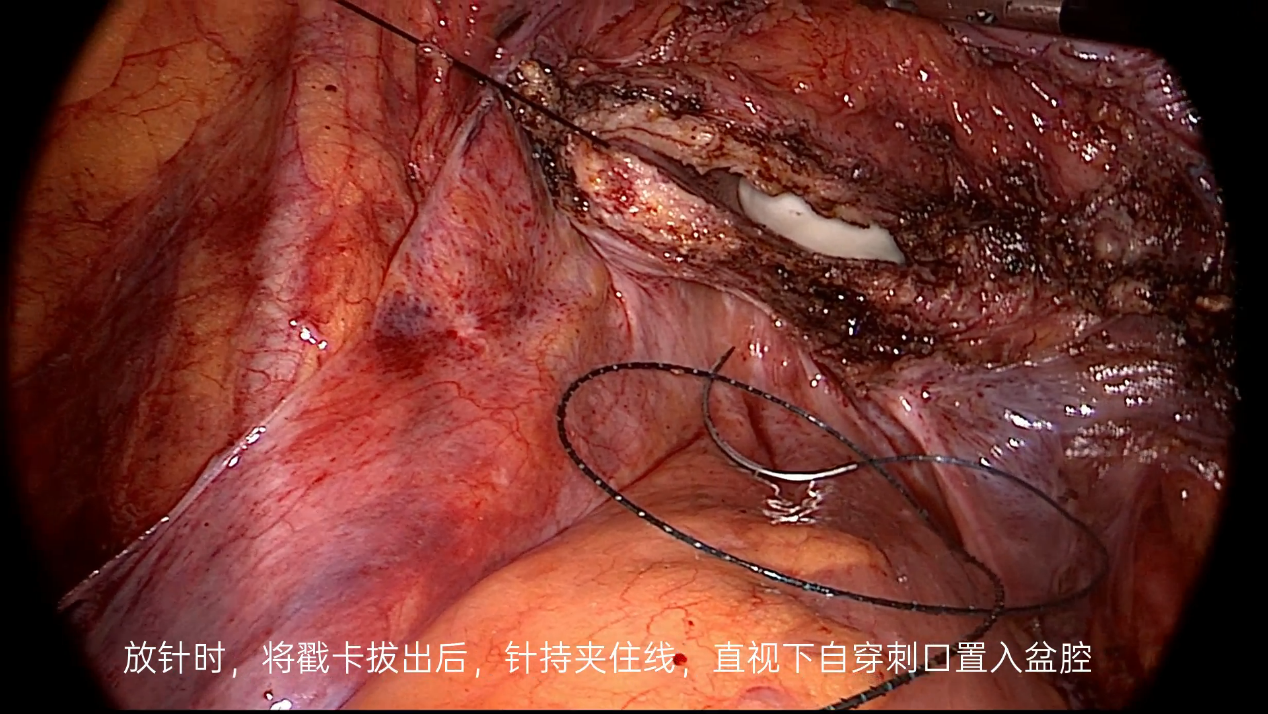

5.3 下面用图片及视频为大家展示阴道残端缝合的详细步骤。

图19

图20

图21

图22

图23

图24

图25

图26

图27

图28

图29

图30

图31